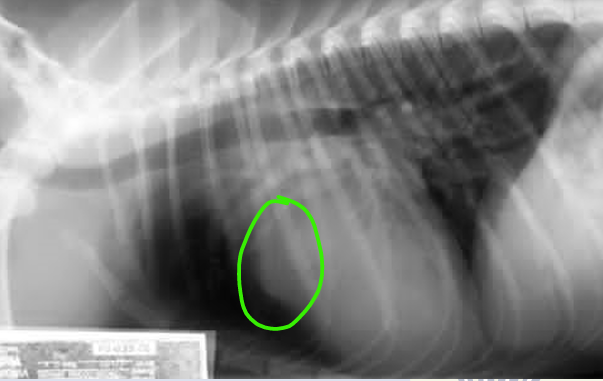

Interstitial pattern

aorta and vena cava is blurry